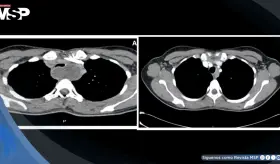

La compresión de la arteria coronaria principal izquierda (LMCA) por dilatación de la arteria pulmonar representa una complicación subdiagnosticada de la hipertensión pulmonar severa, con prevalencia del 6%.